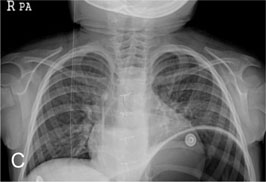

Fig. 1-C

Incomplete removed TIVD

Fig. 1-C Incomplete removed TIVD